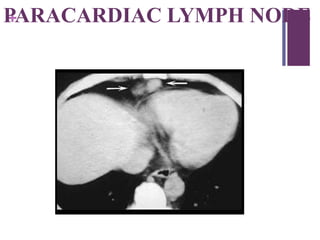

+PARACARDIAC LYMPH NODE